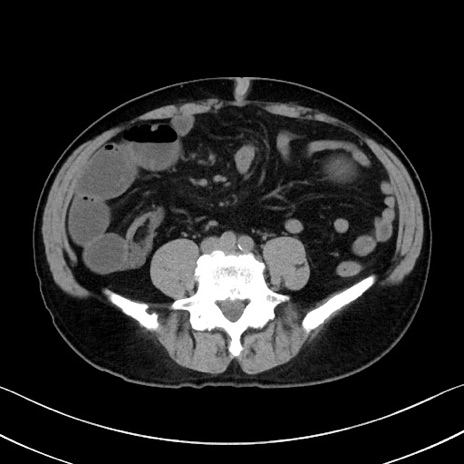

症例35(横断像)

【症例】70歳代 男性

【主訴】腹部膨満、嘔吐

【現病歴】昨日より腹部膨満感出現。本日増悪し、仙痛出現。嘔吐あり、受診。

【既往歴】糖尿病、胆摘後

【身体所見】BP 149/80mmHg、HR 74/min、BT 35.9℃、腹部:膨満、軟、圧痛なし。腸雑音減弱あり。上腹部正中切開瘢痕あり。

【データ】WBC 13500、CRP 1.72